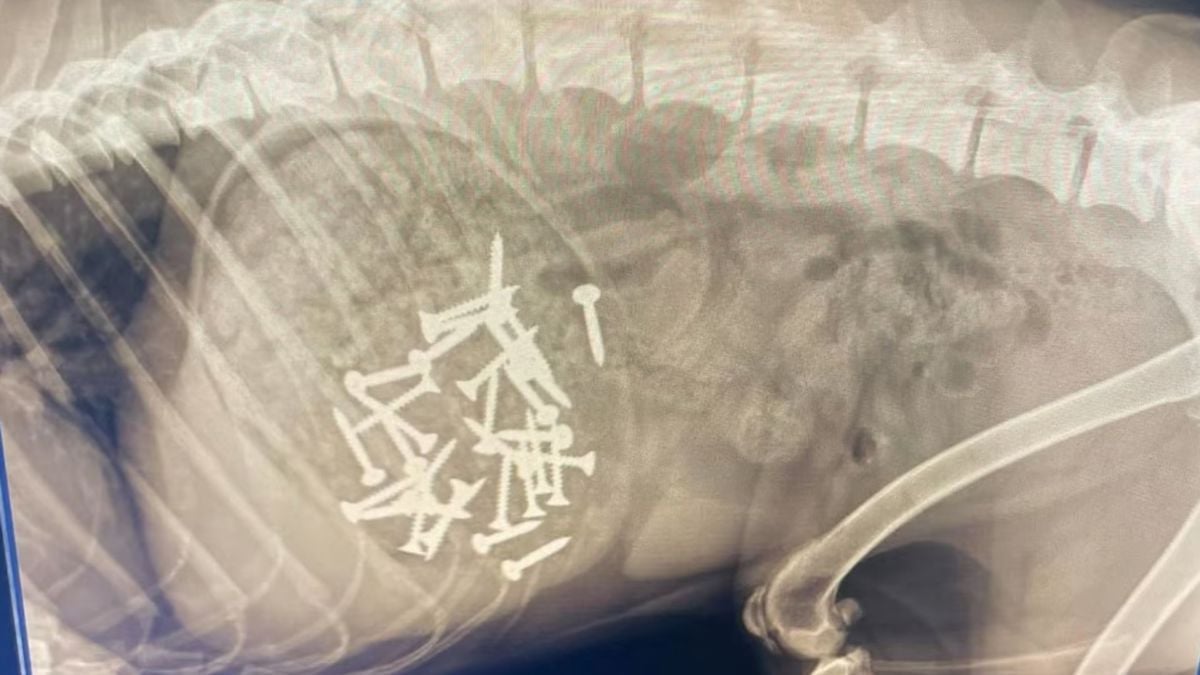

Son chien se comporte bizarrement, elle découvre... une trentaine de vis dans son estomac